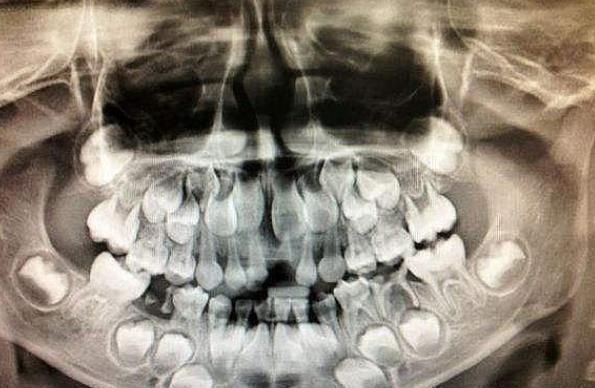

6岁的他从小就和爷爷奶奶一起长大。不久前他换了一颗牙,今天长出来了。但没过多久,他就说受不了牙痛,新牙自动脱落,这让爷爷奶奶很伤心。所以他不得不带他们去医院检查。医生的检查也是CT和MRI,最后得出结论是牙龈癌,牙龈根部已经死了。

医生怒斥爷爷奶奶,你们是怎么带孩子的,孩子这么小不能每天都喝饮料,每天都吃甜食和一些不健康的食物,这类食物饮料对牙齿的伤害特别大,而且里面还含有过量的食品添加剂,会影响到孩子的健康。